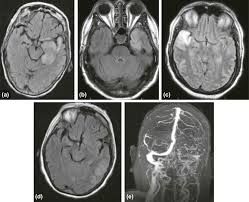

Two subtypes are recognised which differ in demographics, virus, and pattern of involvement. Mri demonstrates extensive edema in the right temporal lobe with areas of intrinsic high t1 signal, in keeping with hemorrhage. Terminology the entity or closely related variants have also been. Coccidioidal meningitis refers to central nervous system involvement of the dimorphic fungus coccidioides spp, mainly coccidioides immitis and coccidioides posadasi. Note the high signal in the caudate heads and putamen on flair.

Pcr was repeated on the biopsy specimen and was positive for hsv. Limbic encephalitis, mca ischaemia, tumours, effects of seizures) hyperintense t2 signal in the medial temporal lobes, inferior frontal lobes and insula basal ganglia are usually spared Axial t2 prominent swelling, increase t2 signal involving the left temporal lobe and insular cortex. Multilocularis, and describes a spectrum of disease involving the spinal cord, the spine, or both. Mri is the diagnostic modality of choice abnormal in 90%; A brain biopsy was performed and the histology was consistent with encephalitis. Mri demonstrates extensive edema in the right temporal lobe with areas of intrinsic high t1 signal, in keeping with hemorrhage. For a general discussion, and for links to other system specific manifestations, please refer to the article on hydatid disease.

The basal ganglia are usually spared. Mri is the diagnostic modality of choice abnormal in 90%; Hsv encephalitis | radiology case | radiopaedia.org. Axial t2 prominent swelling, increase t2 signal involving the left temporal lobe and insular cortex. For a general discussion, and for links to other system specific manifestations, please refer to the article on hydatid disease. Herpes simplex (hsv) encephalitis is the most common cause of fatal sporadic fulminant necrotizing viral encephalitis and has characteristic imaging findings. Herpes simplex virus (hsv) is a human herpesvirus that causes hsv encephalitis (hse), which is the commonest fatal sporadic encephalitis in humans. Hse may result from primary infection or reactivation from latency, and it frequently involves frontal or temporal lobes, as well as the brain stem. The differential diagnoses include limbic encephalitis (paraneoplastic), gliomatosis cerebri, and status epilepticus. A brain biopsy was performed and the histology was consistent with encephalitis. For a general discussion, and for links to other system specific manifestations, please refer to the article on hydatid disease. Cerebral malaria is a rare intracranial complication of a malarial infection. Bilateral temporal lobe t2 hyperintensity refers to hyperintense signal involving the temporal lobes on t2 weighted and flair imaging.

The changes spare the basal ganglia, a feature which is helpful in distinguishing an mca infarct with hemorrhagic transformation from herpes simplex encephalitis, the diagnosis in this case. Hse may result from primary infection or reactivation from latency, and it frequently involves frontal or temporal lobes, as well as the brain stem. Herpes simplex (hsv) encephalitis is the most common cause of fatal sporadic fulminant necrotizing viral encephalitis and has characteristic imaging findings. It is usually bilateral but asymmetrical. The differential diagnoses include limbic encephalitis (paraneoplastic), gliomatosis cerebri, and status epilepticus. Two subtypes are recognized which differ in demographics, virus, and pattern of involvement. Given the history of fever and seizures coupled with the mri findings of bilateral mesial temporal lobe changes, herpes encephalitis requires clinical consideration. Spinal hydatid disease is an uncommon manifestation of hydatid disease, caused by the larval stage of echinococcus granulosus, or less commonly e. Multilocularis.the larval stage is the cause of hydatid disease in humans 1. The differential diagnoses include limbic encephalitis (paraneoplastic), gliomatosis cerebri, and status epilepticus. Herpes simplex encephalitis (hse) is the most common form of viral sporadic encephalitis and, when left untreated, has a mortality rate of 70% (3, 22). This patient went on to have hsv encephalitis proven on csf pcr. Bilateral temporal lobe t2 hyperintensity refers to hyperintense signal involving the temporal lobes on t2 weighted and flair imaging.